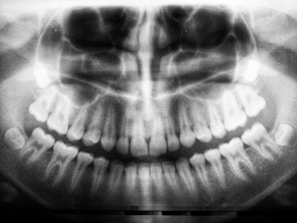

radio diagnostic

Imagerie dentaire numérique pour un diagnostic précis et rapide.

Moins de rayons, plus de sécurité.

Un plateau technique complet permettant la prise en charge de tous types de soins

(chirurgie, soins conservateurs, prothèses, implantologie, orthodontie) et l'utilisation de matériel d'imagerie de pointe (radio panoramique et rétroalvéolaire).